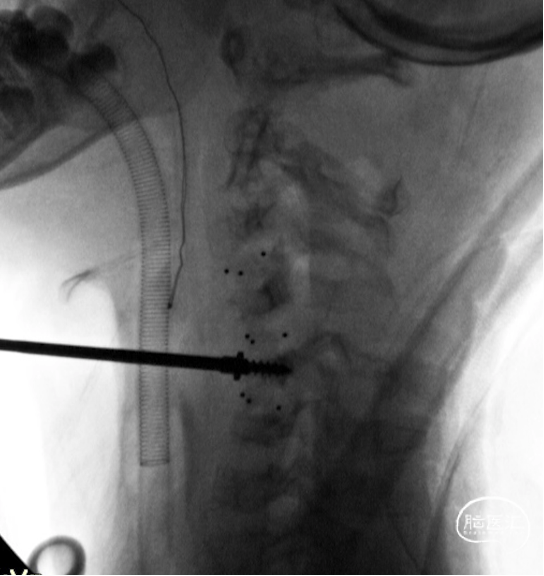

首先行后路手术,切除双侧C5绞锁的上关节突

C4-5置入牵开钉,可见椎体只能容纳一个牵开钉宽度